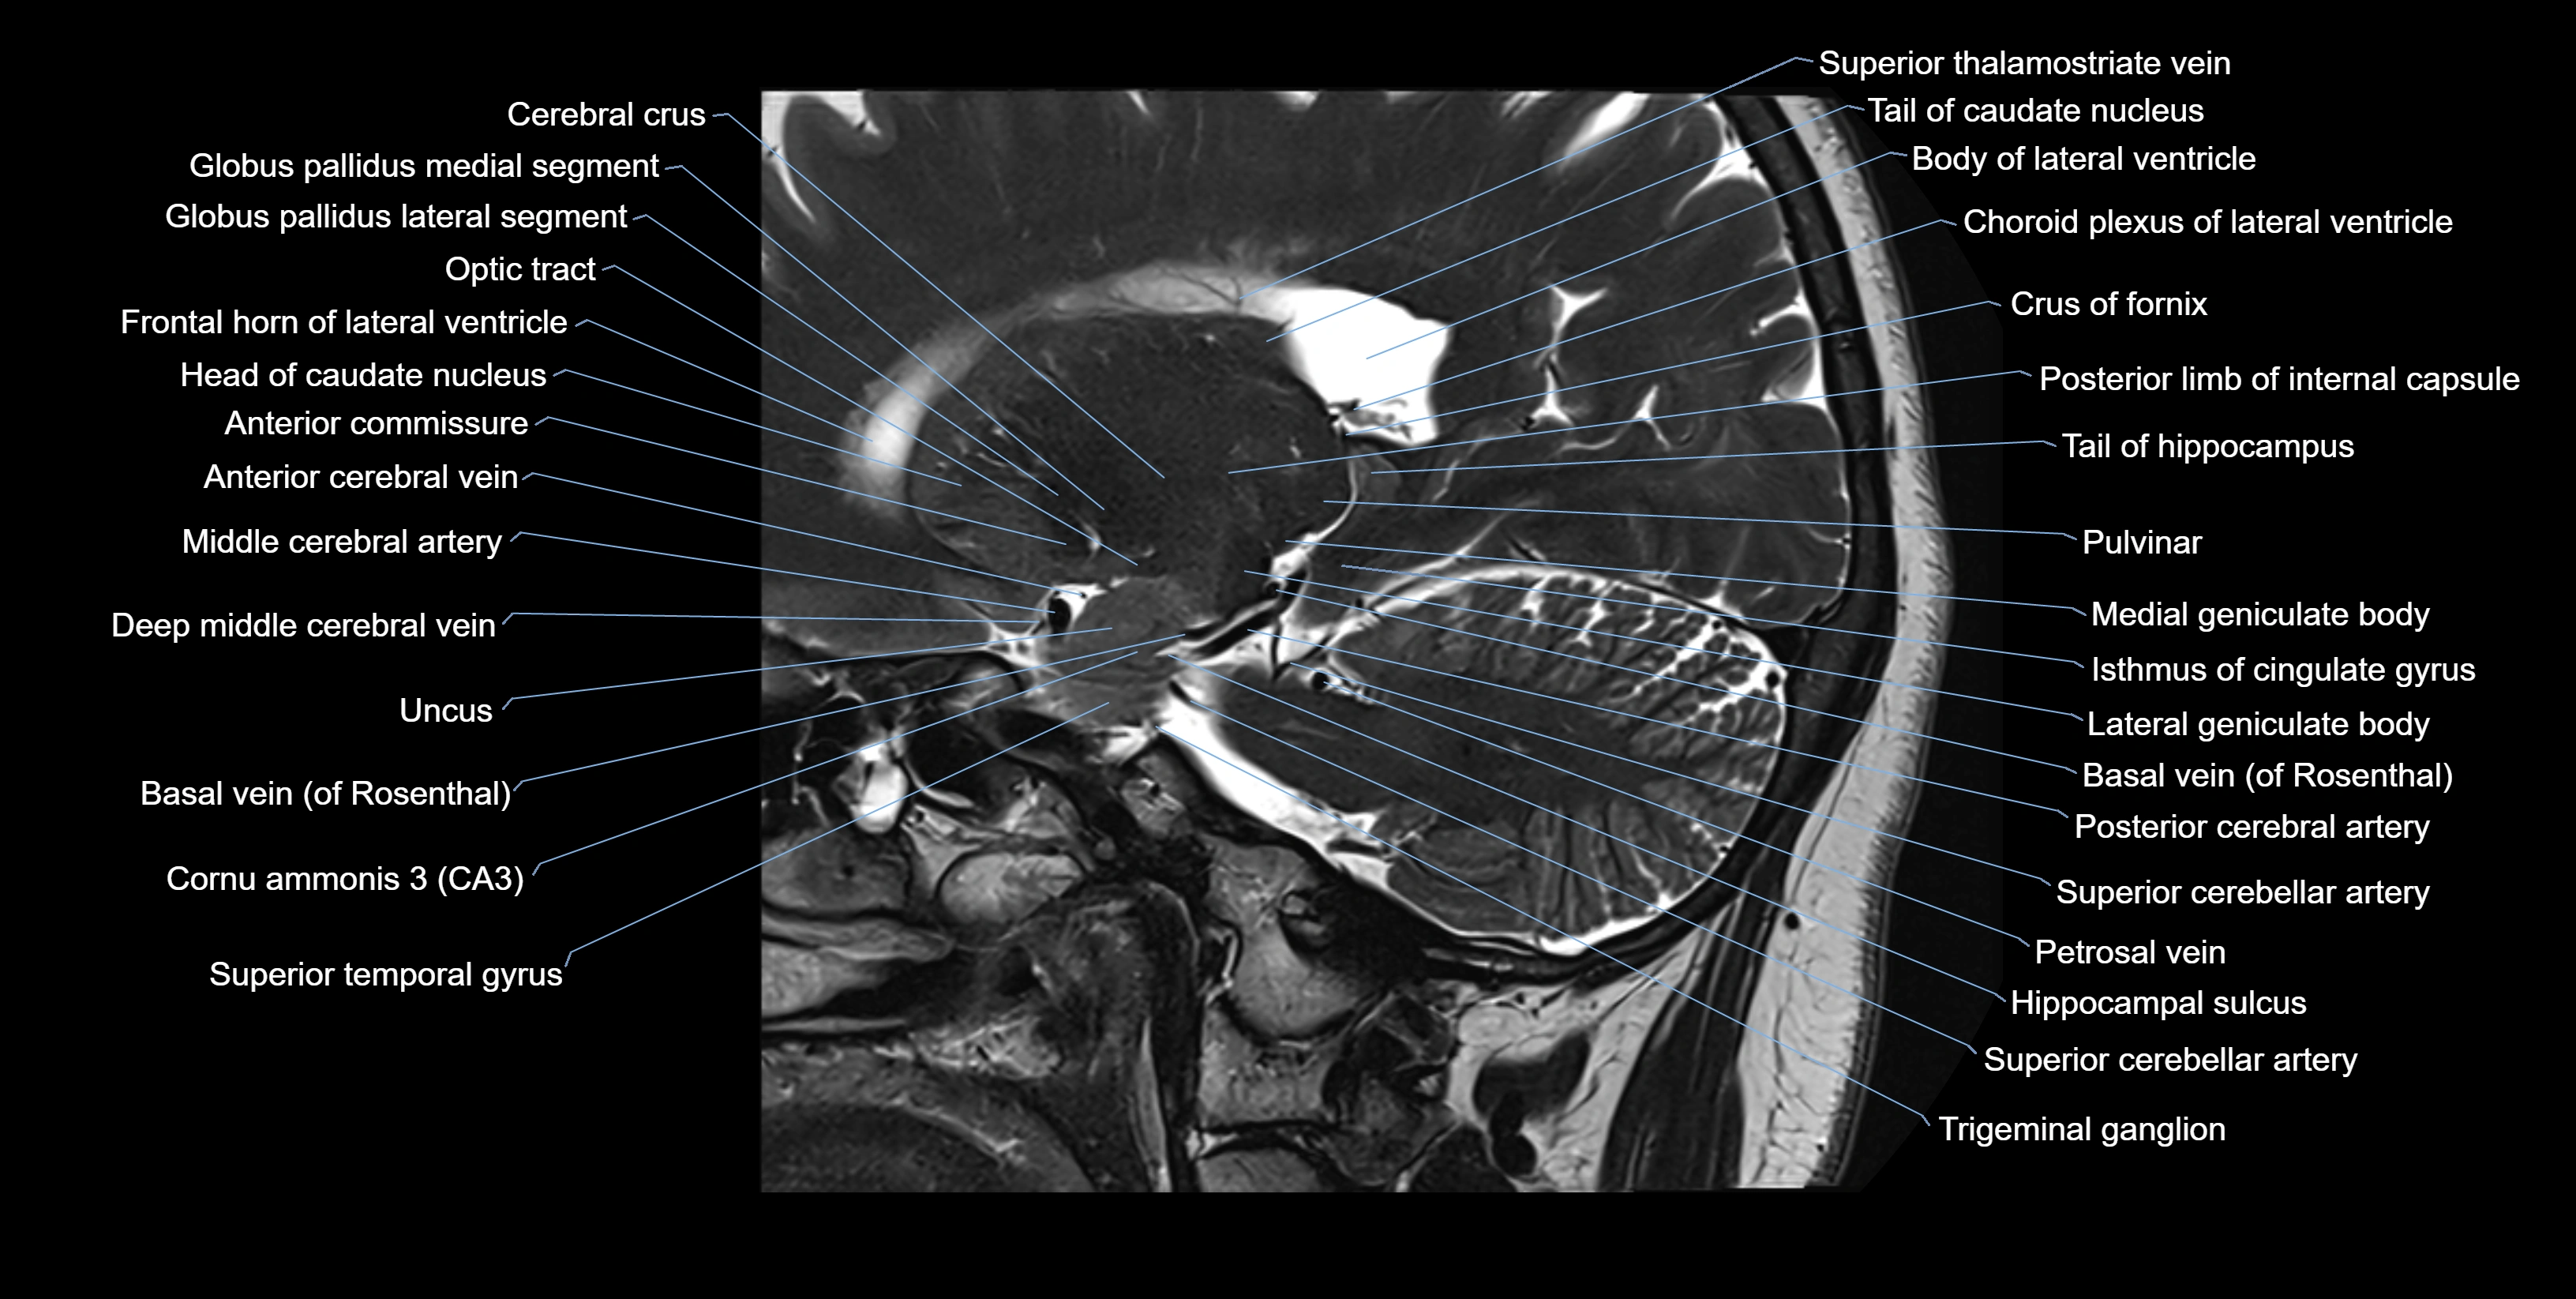

The alveus of the hippocampus is a thin, white matter layer covering the superior (ventricular) surface of the hippocampus within the temporal horn of the lateral ventricle. It consists of myelinated efferent fibers arising primarily from the pyramidal neurons of the hippocampus. These fibers converge medially to form the fimbria of the hippocampus, which continues posteriorly into the fornix, forming a crucial part of the Papez circuit involved in memory consolidation and emotional processing.

The alveus serves as the initial output pathway of the hippocampal formation, linking it to other limbic structures including the hypothalamus, mammillary bodies, and cingulate gyrus. Because of its intimate relationship with the hippocampal head and tail, it is often evaluated in cases of temporal lobe epilepsy, hippocampal sclerosis, and neurodegenerative diseases.

Location and Structure

• Position: Lies on the ventricular (superior) surface of the hippocampus, beneath the ependyma of the inferior horn of the lateral ventricle.

• Composition: A thin sheet of myelinated axons derived mainly from hippocampal pyramidal cells.

• Course: Fibers run medially along the hippocampal surface to form the fimbria of the hippocampus, which curves upward and backward into the fornix.

• Relations:

• Superiorly: Ependyma and CSF of the temporal horn of the lateral ventricle

• Inferiorly: Pyramidal cell layer of the hippocampus (CA1 region)

• Medially: Fimbria and fornix

• Laterally: Temporal lobe white matter and parahippocampal gyrus

Clinical Significance

• Hippocampal sclerosis: Common in temporal lobe epilepsy; the alveus may appear thinned or with altered signal intensity.

• Atrophy: Seen in Alzheimer’s disease and medial temporal lobe atrophy syndromes.

• Tumor invasion: Gliomas or metastases may involve the hippocampal alveus region.

• Surgical relevance: Key landmark in selective amygdalohippocampectomy procedures.

• Imaging relevance: Evaluated in volumetric hippocampal MRI, epilepsy mapping, and neurodegenerative disease imaging.